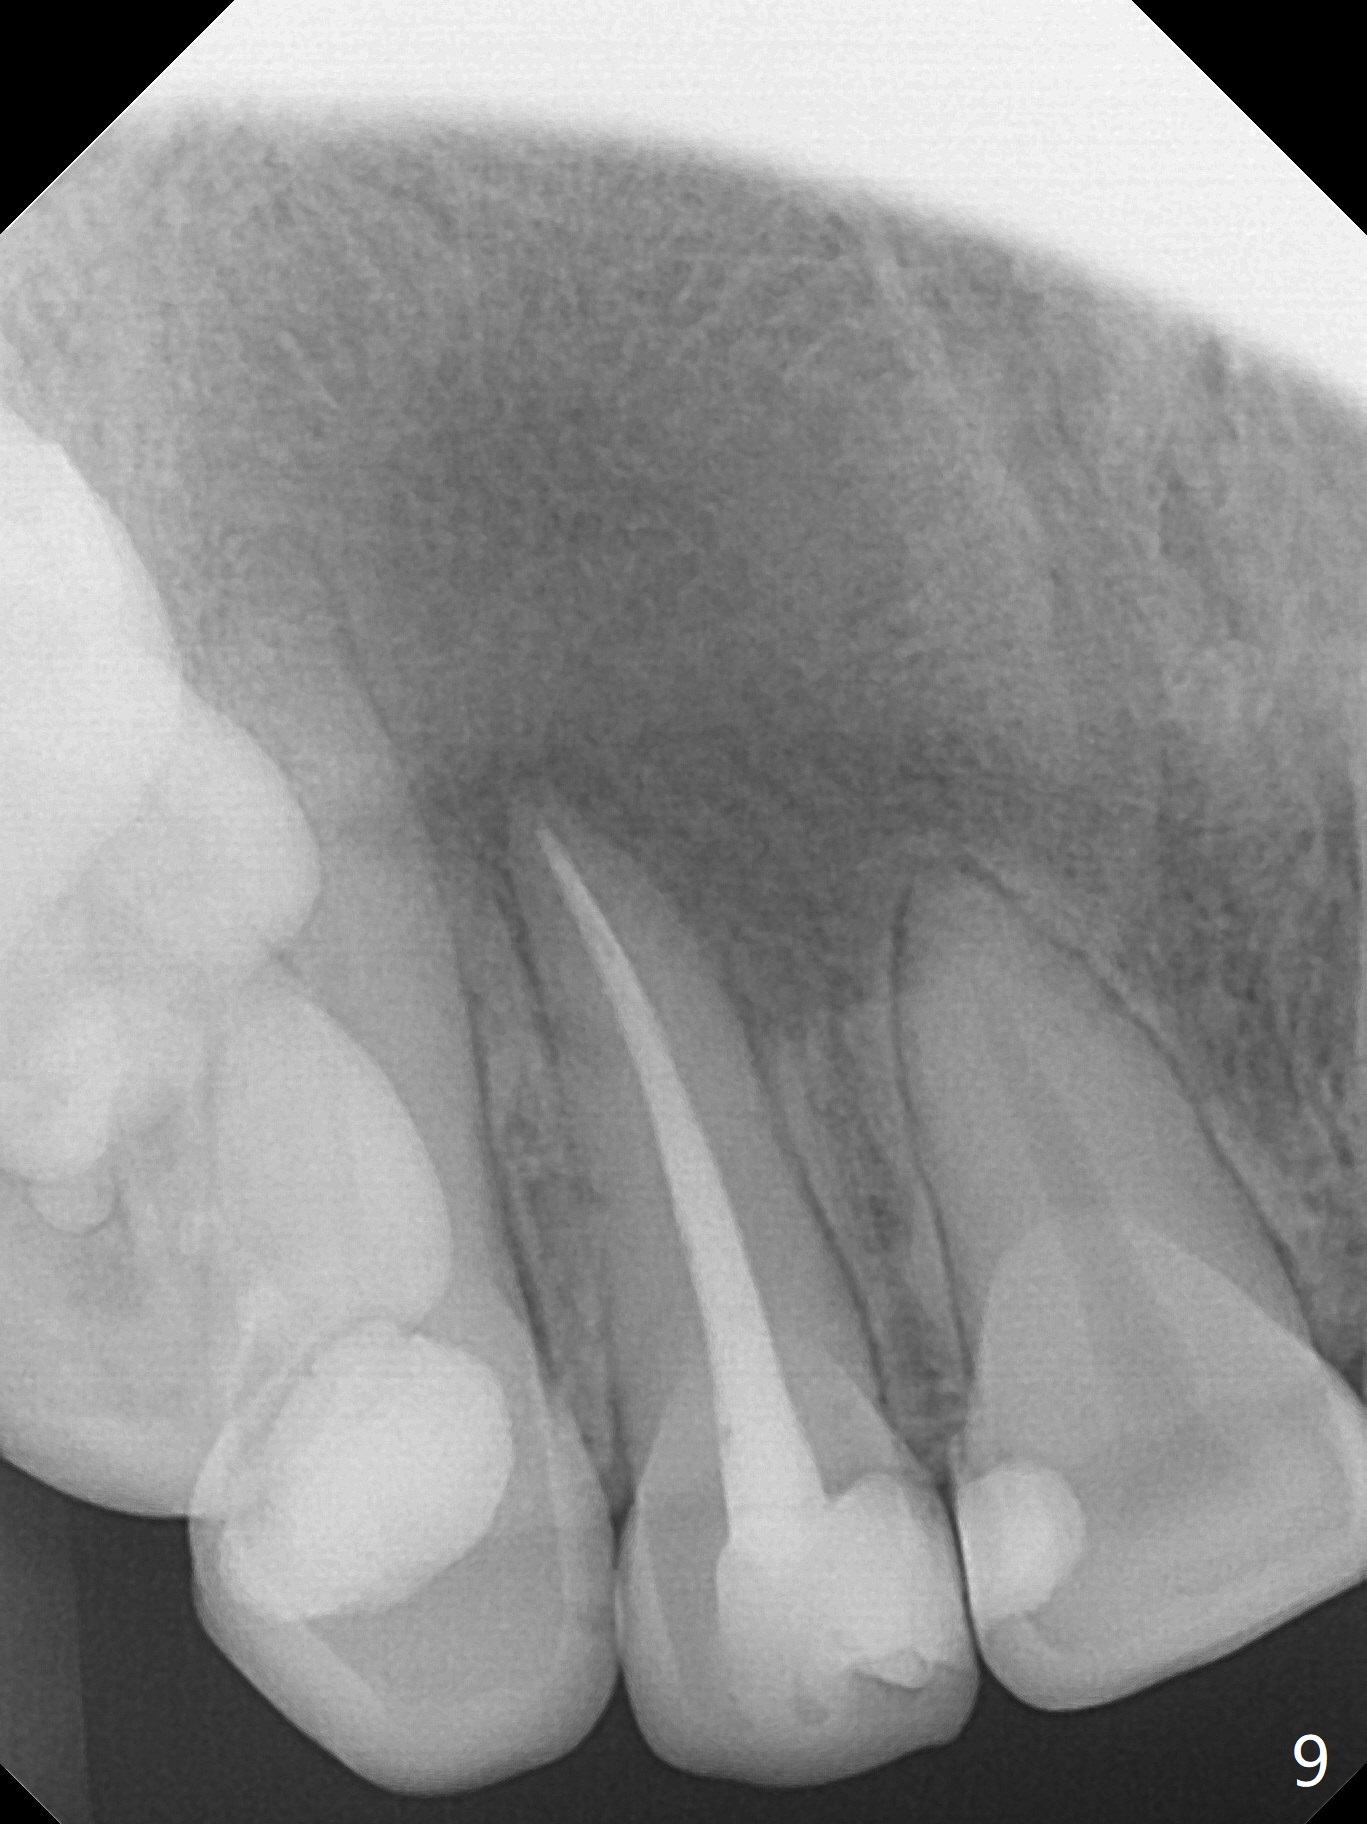

When this patient returns with improvement of symptoms, RCT will be finished. In fact the swelling relapses a month later (Fig.6). After discussion of possible cyst enucleation and increase in debridement from 30/.04 to 40/.06, a master cone of 40/.06 is inserted (Fig.7) and RCT is finished (Fig.8). Although the patient reports relapse of swelling, the palate looks normal and bone density increases 7 months postop (Fig.9). For 14 implant placement, CT is taken 2 years 1 month post RCT (Fig.10,11). Radiolucency is confined to the apex of the tooth #7 (white *). The labial concavities mesial and distal to the left lateral incisor makes radiolucencies (bone loss) look more radiolucent, creating globumaxillary cyst image. The globumaxillary cyst is a terminology for its shape. It does not mean congenital in nature. The treatment is dependent upon vitality test of the involved teeth.